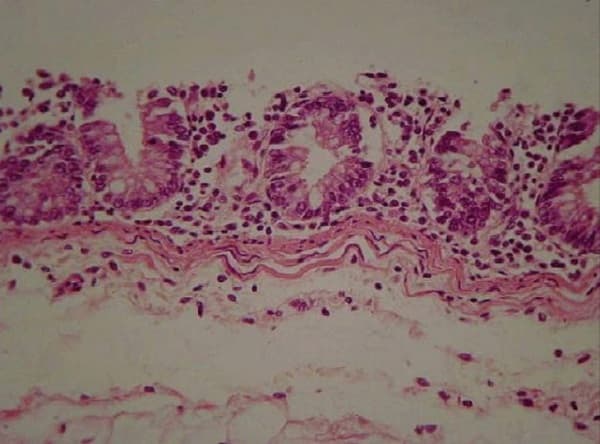

Figura 2. Corte histopatológico a nivel de íleon

El 8% de los animales presentaron cuadros de diarrea y pérdida de condición. Se sacrificaron cuatro animales observándose en la luz intestinal del íleon la presencia de masas gelatinoides rojizas con fluido; y en otros sectores, masas amarillentas adheridas a la mucosa, además de pseudomembranas mucosas y aparente leve engrosamiento de las capas musculares. En el análisis histopatológico se observó necrosis y atrofia de las vellosidades intestinales, dilatación y ramificación de las criptas con infiltración de neutrofilos en el lumen (Fig. 2). En otras secciones se observó en las vellosidades intestinales una leve proliferación de enterocitos inmaduros, escasas células caliciformes, epitelio descamado, severa necrosis de la glándula de Lieberkhün, infiltración de mononucleares en el corion, y hacia la luz, restos de células descamadas, depósito de fibrina y presencia de una flora mixta de microorganismos cocobacilares basófilos y espiralados; estos últimos positivos a la técnica de WarthinStarry (Fig. 3).

Se puede concluir que los animales que resultaron seropositivos con la prueba IFI habrían tenido un desafio de campo con L. intracellularis, ya que obtuvo una seroprevalencia del 38.7%, y donde el mayor porcentaje de animales afectados ocurrió en la etapa de engorde. Además, se observaron diversas lesiones macroscópicas ileales, y en los cortes histopatológicos de íleon se encontraron lesiones compatibles con ileitis necrótica producida por L. intracellularis.